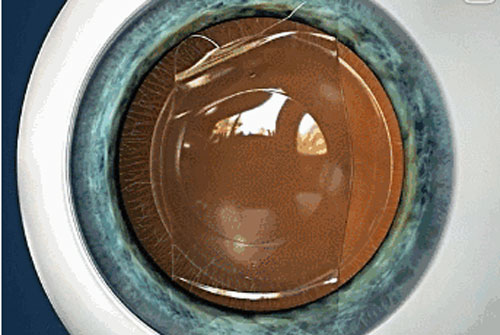

ICL晶體植入手術(shù)無需切削角膜組織,而是將小小的“眼鏡”植入眼內(nèi),具有可逆性,適合近視1800度以內(nèi)、散光600度以內(nèi)的高度近視者,還可一次性解決散光、遠(yuǎn)視、老花等問題。